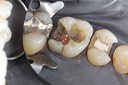

Matt Dodson #31 pre-op

Matt Dodson #31 amalgam removal

Matt Dodson #31 prep

Matt Dodson #31